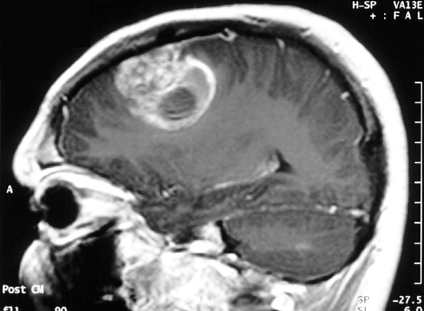

Glioblastoma is the most common and malignant form of brain cancer. Each year, around 3,200 patients are diagnosed with this disease in the UK and the Netherlands. Despite improving knowledge of its genetic causes, it remains stubbornly incurable, with current treatment schedules resulting in an average survival of 12 months from diagnosis. Part of the poor prognosis is due to tumour heterogeneity: different parts of the tumour have different characteristics and will respond differently to therapy. As a result, a particular treatment may kill some of the tumour cells, while others cells continue to grow.